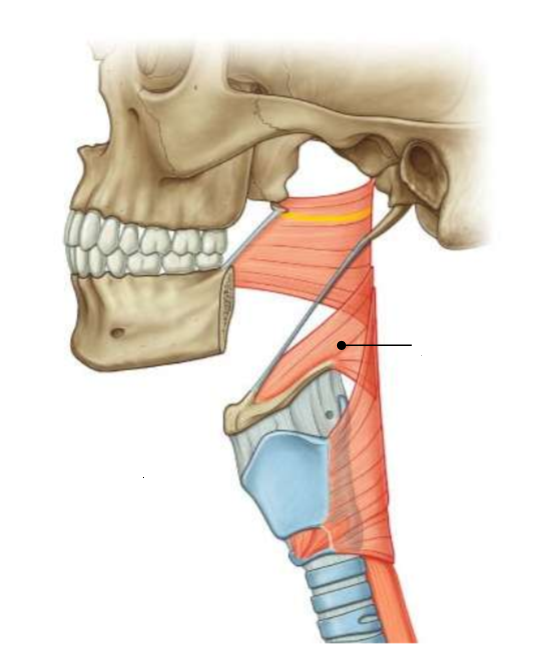

What is this muscle?

middle constrictor

What are the attachments of this muscle?

lower stylohyoid ligament, lesser and greater horns of hyoid → pharyngeal raphe

What muscle is this?

inferior constrictor

Which part of the muscle is 1?

thyropharyngeus

Which part of the muscle is 2?

cricopharyngeus

What are the attachments of this muscle?

oblique line of thyroid cartilage, cricothyroid tendon, cricoid cartilage → pharyngeal raphe